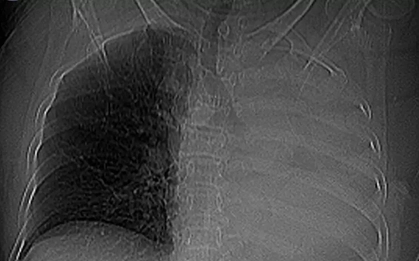

Chỉ vươn vai buổi sáng, nam sinh 17 tuổi bị “xẹp phổi”

Không va chạm, không chấn thương, chỉ một động tác vươn vai sau khi ngủ dậy, vậy mà phổi lại “thủng”? Câu chuyện tưởng như khó tin này vừa xảy ra.

Sặc một viên thuốc, cụ bà xẹp toàn bộ phổi trái

Tối 18/1, Bệnh viện Đa khoa khu vực Quảng Nam (thành phố Đà Nẵng) cho hay đã tiếp nhận một bệnh nhân nhập viện trong tình trạng ho nhiều đột ngột kèm khó thở sau khi uống thuốc.

Đang khỏe mạnh bỗng bị xẹp phổi, thanh niên 24 tuổi hối hận vì đã làm 1 điều suốt gần 10 năm

Chỉ một thói quen mà nhiều người trẻ tưởng là “vô hại” đã khiến nam thanh niên 24 tuổi phải đối diện với nguy cơ tử vong do xẹp phổi.

Người đàn ông xẹp phổi chỉ sau 20 lần chống đẩy và nhảy dây, bác sĩ cũng bị sốc

Các bác sĩ đã vô cùng sốc trước trường hợp một người đàn ông bị tràn khí màng phổi sau 20 lần chống đẩy và vài phút nhảy dây.

Bé 8 ngày tuổi bị xẹp phổi phải, viêm phổi nặng vì hành động yêu thương của người thân

Cấp cứu trong tình trạng tím tái, khó thở, xẹp toàn bộ phổi phải do nhiễm virus hợp bào hô hấp RSV, sau 5 ngày em bé đã thoát khỏi "cửa tử".

Long An: Ném cát đùa giỡn với bạn, bé trai 6 tuổi hít phải miếng nhựa vào mũi gây xẹp phổi nguy kịch

Hít sặc phải mẫu nhựa cứng khi chơi ném cát cùng bạn, bé trai bị bít lòng phế quản đoạn sâu và xẹp toàn bộ nửa phổi phải, tình trạng rất nguy kịch.